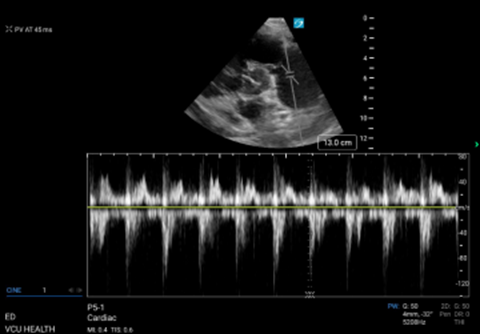

Pulmonary acceleration time (PAT); or pulmonary artery acceleration time (PAAT)) is the time it takes for blood flow into the pulmonic trunk to reach maximum velocity. PAT is shorter when pulmonary arterial resistance is increased. Starting in a parasternal short view, the probe is fanned superiorly to find the RVOT above the aortic valve. The pulsed wave (PW) doppler gate is then placed just proximal to the pulmonic valve and velocity tracing generated. (Figure 3) PAT is the time from the start of flow to the peak, normal values being greater than 60msec. An abnormally short PAT (<60msec) suggests an abnormally increased pulmonary arterial resistance. The patient in this case had a PAT of 45ms, and an abnormal waveform demonstrating a mid-systolic notch. While the distinction can be difficult, an early systolic (ESN) occurs in the first half of systole and is more indicative of PE, while a mid- or late-systolic notch points towards PAH.

Figure 3. PW doppler of RVOT with measurement of PAT.